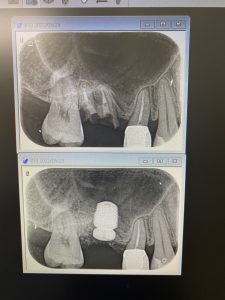

さて、本日は右上6番のソケットリフト 残存骨は0.5ミリ〜1.5ミリですので、落下させない事に1番気を遣います

本日も、定番の人工骨を使わない、デンサーバーでの挙上です 切開から埋入まで15分で終了 この手法はとにかく早い! 鉄板です!!

本日の症例は骨が硬いので新しいデンサーバーを使い効率良く圧縮、飛散が出来ましたね 午後も楽しみな症例あるから 気持ちウキウキ..笑 昼寝しましょう〜